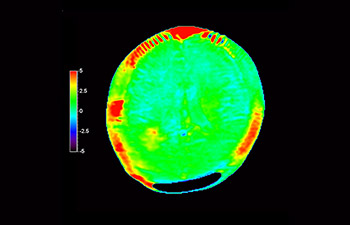

In a society where neurological disorders represent a heavy burden, Philips is committed to provide superb diagnostic clarity and treatment guidance for all patients. Today, although MR is the gold standard in neuro oncology imaging, its accuracy in tumor grading and treatment follow up assessment can be further improved. 3D APT (Amide Proton Transfer) is a unique, contrast-free, brain MR imaging method addressing the need for more confident diagnosis in neuro oncology. 3D APT uses the presence of endogenous cellular proteins, to produce an MR signal that directly correlates with cell proliferation, a marker of tumoral activity. 3D APT can support trained medical professionals in differentiating low grade from high grade gliomas and, in differentiating tumor progression from treatment effect1.

with 3D APT